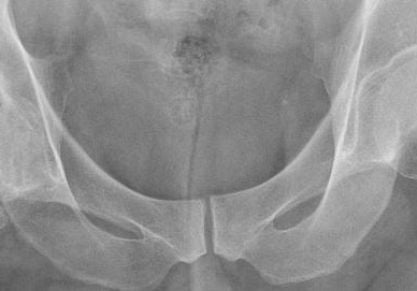

Операция по замене тазобедренного сустава: обо всем по порядку

Как делают операцию по замене тазобедренного сустава? Подготовка, противопоказания, последствия, реабилитация. Видео. Стоимость. Отзывы.

История основания эндопротезирования тазобедренного и коленного суставов

Что такое эндопротезирование, и какие могут быть показания к его проведению? История основания эндопротезирования суставов, благодаря трудам ученых, начиная с конца 19 века. Цементный и бесцементный способы фиксации протезов. Из...